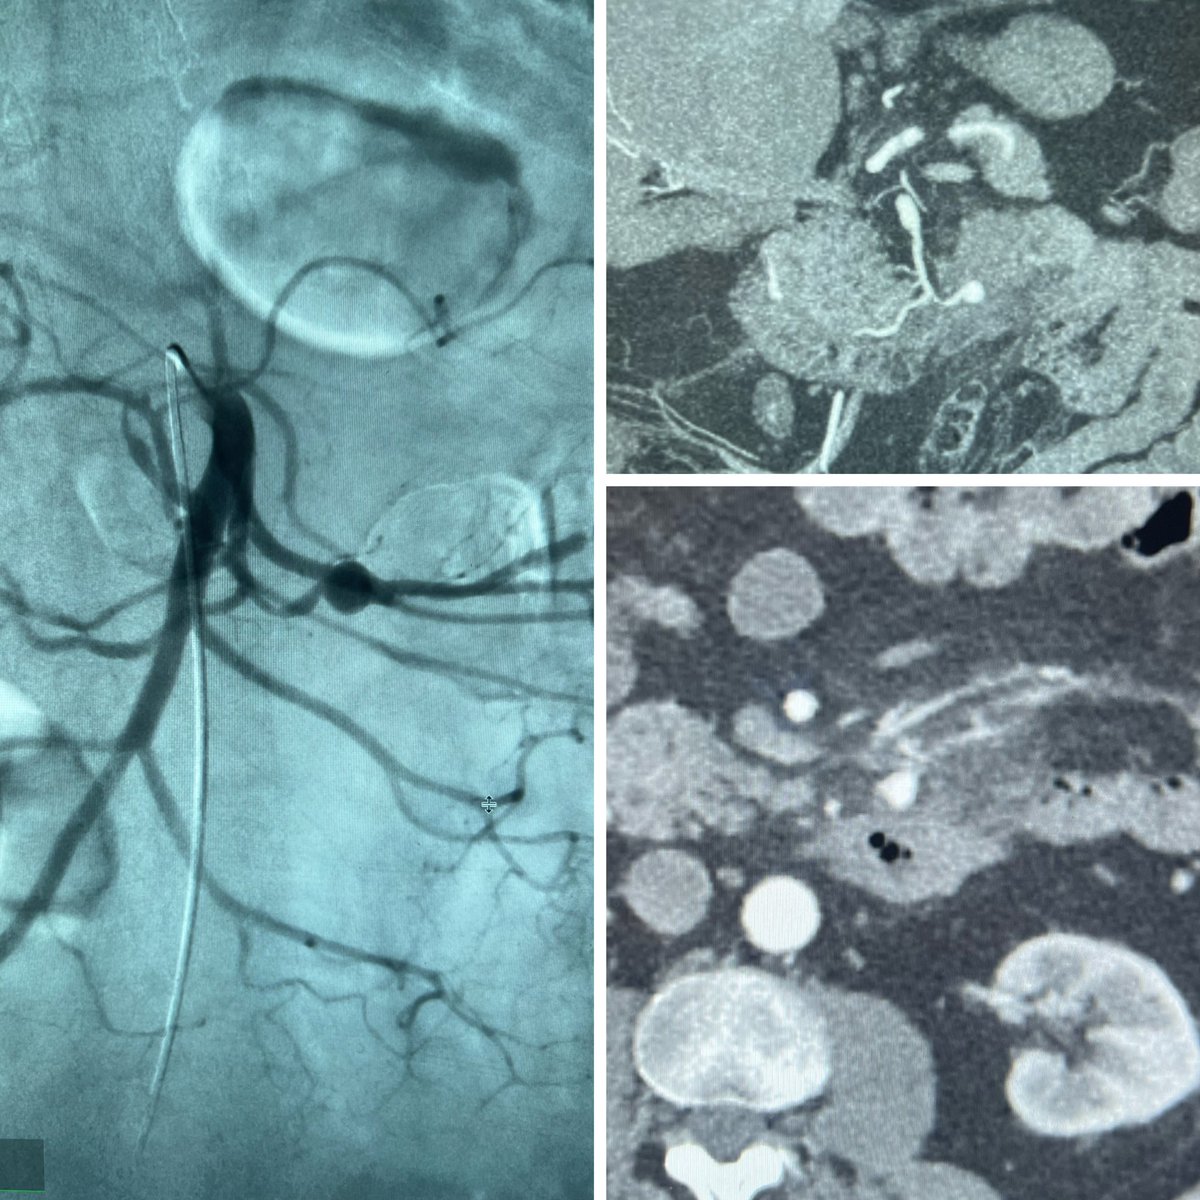

Transcatheter arterial #embolization is the first line treatment for AMLs. This case was done trans-radial using ethanol/lipiodol mix (1:1 ratio) injected through an #Occlusafe microballoon catheter. #Irad

Massive but slowly bleeding AML. Love liquid Embolics for this. Lipiodol, ethanol, Gelfoam and contrast. #IRAD Now you see it, now you don’t.

It was GU week this week. AVM/AVF with 3 feeders. Two largest embolized with #Embold. Glue for the smallest branch. Now you see it now you don’t!